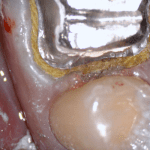

In this clinical video we demonstrate how to scan a molar preparation for the replacement of a crown with recurrent decay and open margins. The molar was root canal treated and the tissue was inflamed. the preparation was imaged and a temporary was fabricated to allow the tissue to heal properly.

The main point of this video is to show how to capture the contacts of the adjacent teeth and the deep marings